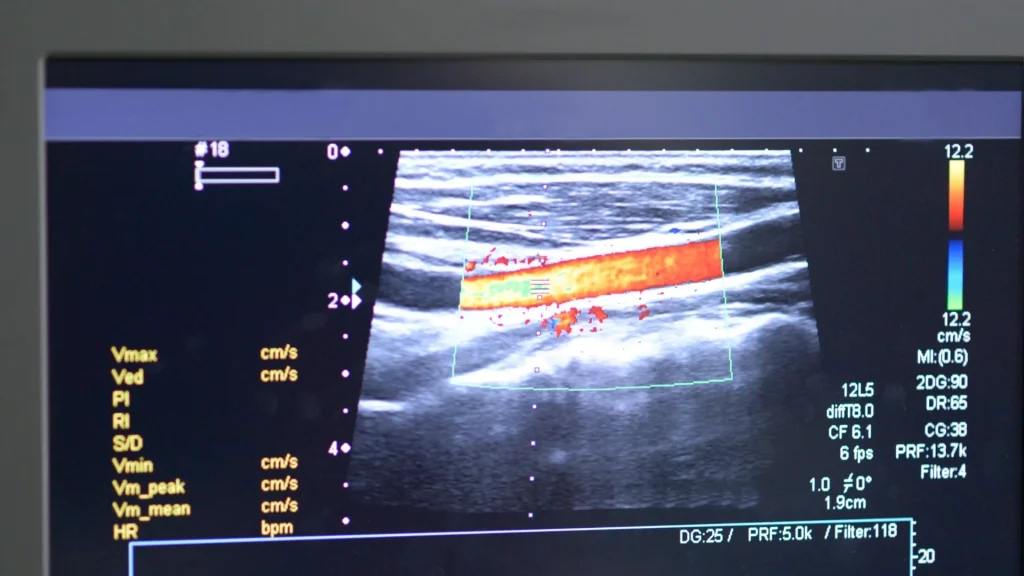

AI secara signifikan meningkatkan kualitas visualisasi pada hasil USG. Algoritma pemrosesan gambar dapat mengurangi gangguan visual dan mempertegas struktur organ. Hasil citra yang lebih tajam membantu dokter melihat detail yang biasanya terlewat, terutama pada perangkat portable.

Salah satu keunggulan besar AI adalah kemampuannya menganalisis citra secara real-time. Saat pemeriksaan berlangsung, AI langsung menampilkan hasil yang sudah dioptimalkan. Hal ini sangat membantu dalam situasi darurat di mana waktu menjadi faktor kritis.